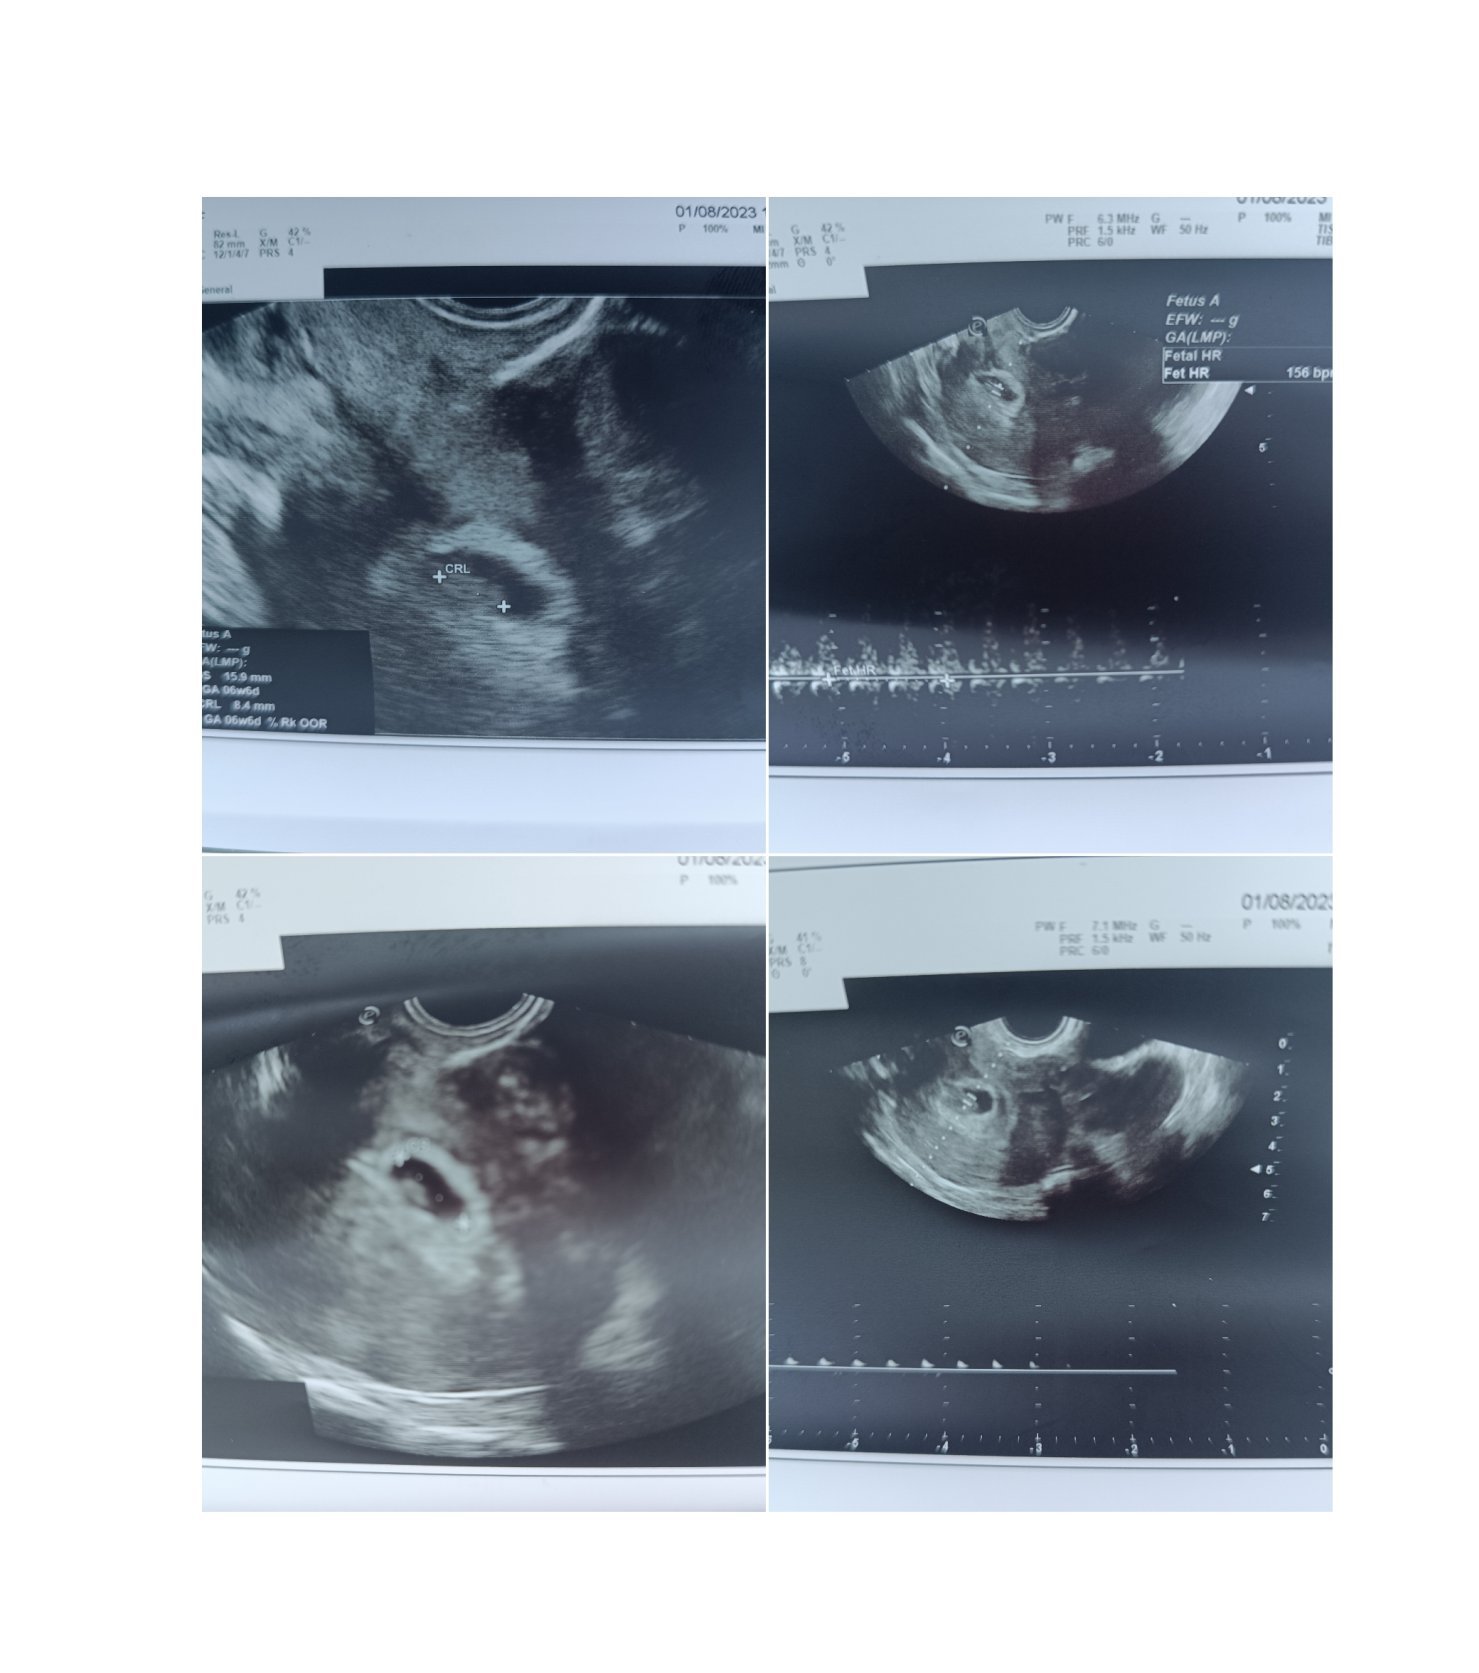

Какви са резултатите от изследванията и прегледите в ранна бременност?